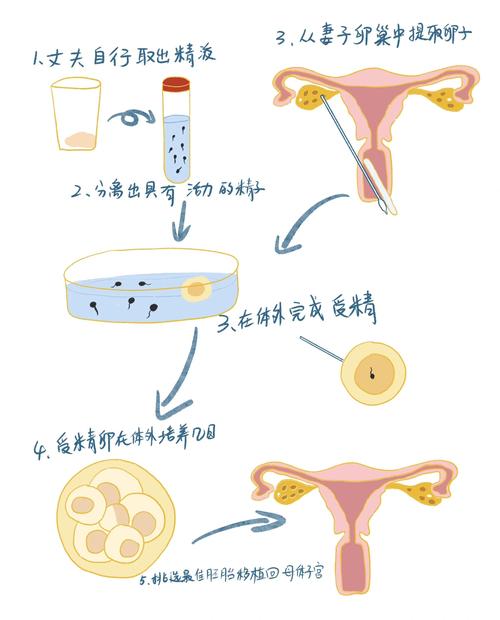

本文从遗传、环境、母体、胚胎、免疫和生活方式等多个角度探讨了试管婴儿生化妊娠的成因,并提供了相关统计数据支持。